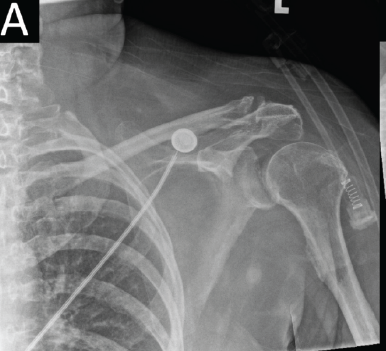

Clavicular Fracture Associated with Subclavian Artery Lesion: Case Report and Review of the Literature

Stef Biesemans , Tom Langenaeken , Joris Duerinckx

………………………………p.62-67